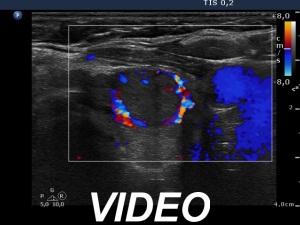

Ultrasonography. The thyroid was moderately hypoechogenic and inhomogeneous. There were multiple echonormal and minimally hypoechogenic discrete lesions in both lobes. Except for the one lesion in the left lobe, these did not correspond to nodule in a pathological sense, while in the event of a minimally hypoechogenic lesion in the left lobe, this possibility could not be excluded.

The patient had a deceptive ultrasound presentation on which the possibility of nodules in a pathological sense could not be excluded. It is worth analyzing the ultrasound images and video.